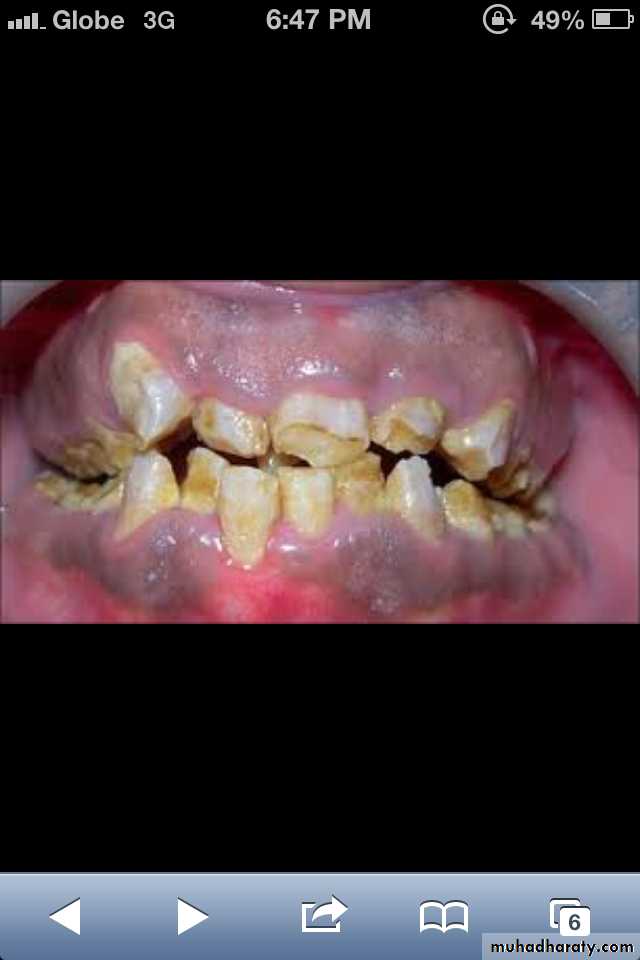

Amelogenesis Imperfecta

*It is a developmental disturbance that interferes with normal enamel formation.*It leads to marked changes in the enamel of all or nearly all the teeth in both dentitions.

*Most forms are autosomal dominant or recessive.

*Affects both dentition.

Enamel is composed mostly of mineral that is formed and regulated by the proteins in it. Amelogenesis Imperfecta is due to the malfunction of the proteins in the enamel.

* Classified based on pattern of inheritance:hypoplasia.

hypomaturation.

hypocalcified.

* No treatment except for improvement of cosmetic

appearance.

Hypoplastic Amelogenesis Imperfecta:

* Due to some defect in ameloblasts enamel fails to develop to its normal thickness dentin exposed the tooth shows yellowish-brown color.*Enamel is randomly:

pitted .

rough OR smooth &glossy.

*The occlusal surfaces of the posterior teeth are relatively

flat with low cusps due to attrition of cusp tips that were initially low and not fully formed. An anterior open bite may be noted. defects become stained but teeth are not especially susceptible to caries unless enamel is scanty and easily damaged.

Generalized hypoplastic type

Amelogenesis ImperfectaAffects primary &permenant dentition

Severe mottling of the enamel surface.

Hypocalcified Amelogenesis Imperfecta:

*Enamel matrix is formed in normal quantity,poorly calcified.

When newly erupted:Enamel is normal in thickness, normal form, but weak , and opaque or chalky in appearance.

With years of function:

Coronal enamel is removed except for cervical portion that is occasionally calcified better.

Radiographically:

Density of enamel & dentin are similar.